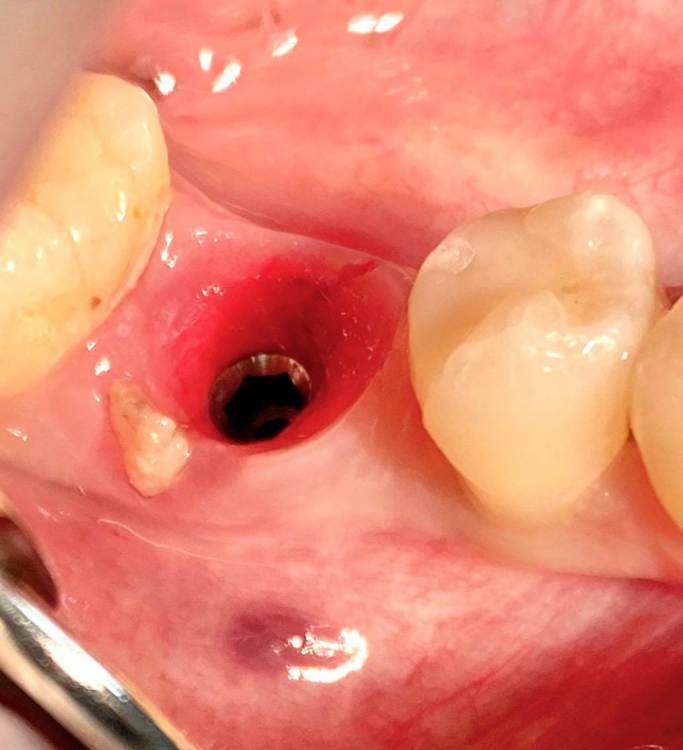

колесников Опубликовано 5 июля, 2022 Поделиться Опубликовано 5 июля, 2022 Здравствуйте коллеги. Год назад попалась публикация где описывался случай как ксеноаугментат секвестрировался спустя 12лет. Мне на днях попался аналогичный случай. Спустя 5 лет(графт bio-oss). Пусковым механизмом, вероятно ,был цемент ,попавший в придесневую шахту после фиксации. Ещё из интересного: интегрированный имплант (mis)удалён ключом на реверс. Вывод: чистый ксено-это не кость. 6 Ссылка на комментарий

колесников Опубликовано 6 июля, 2022 Автор Поделиться Опубликовано 6 июля, 2022 Подтверждаю,альфа био легко удаляется на реверс. Были трёх,пяти и семилетние случаи,все одинаково . Мис впервые,интеграция видимо была,тк был слышен щелчок ломающейся кости. Аналогично легко удалил два случая реплейса. Вот с осстем эта штука не прошла. Был даже случай три месяца после имплантации,ни в какую,только слизывался шестигранник. Зиммер вообще жуть,неудаляемая штука. Ссылка на комментарий